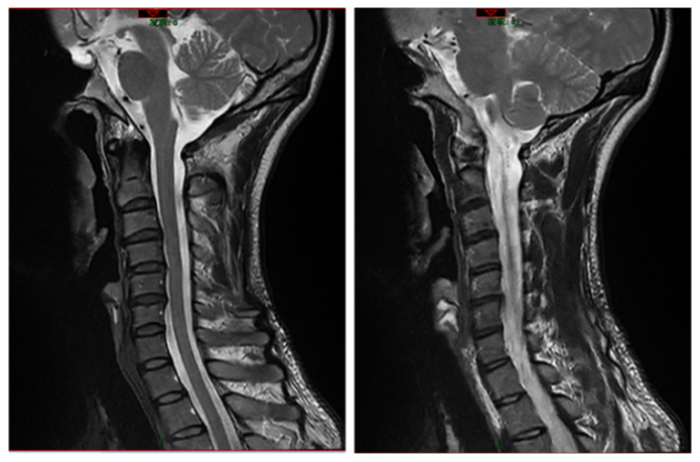

45岁的程序员张先生(化名)最近陷入健康困境:反复发作的颈肩疼痛让他夜不能寐。核磁共振显示仅有轻度椎间盘突出和生理曲度变直,但理疗、针灸、推拿轮番上阵都收效甚微。更让他焦虑的是,疼痛逐渐蔓延至背部和头部,久坐半小时就需起身活动,甚至出现手部麻木症状。持续的颈肩疼痛和头痛导致他工作效率下降,情绪愈发焦躁,陷入"疼痛-焦虑-失眠-疼痛加重"的恶性循环。

在医生的建议下,张先生接受了全面的肌肉功能评估。结果令人震惊——全身肌肉量仅为同龄人标准的68%,核心肌群力量尤其薄弱。原来,由于工作需要久坐少动,导致他的肌肉流失,使脊柱失去"天然护甲",颈椎不稳,椎间盘承受的压力倍增。这种隐匿的肌肉衰减综合征(肌少症),正是他头颈肩痛反复发作的元凶。